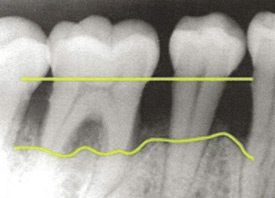

When an extraction is necessary When too much bone around a tooth has been lost due to severe periodontal disease (also called periodontitis), sometimes the best treatment is to remove the tooth to ma....